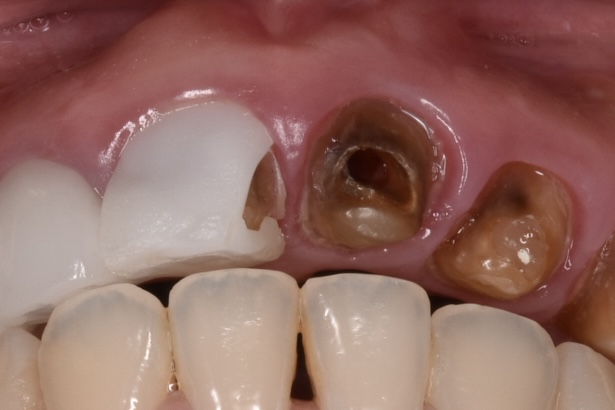

20代女性 20代前半の頃大阪にある有名審美歯科で前歯6本のセラミック矯正治療を受けた。強い痛みはないが、歯茎は赤黒く腫れていて真ん中で割れて、すでに連結してあるセラミックが脱落している状態です。とご相談くださいました。

初診時の状態

白い6連結のセラミックがありますが、右側のセラミックの前歯は破折しています。(写真左)また6連結の中央でジルコニアのフレームごと破折していることも確認できます。(写真中央)左の前歯は神経処置がされておらず穴だけ開いた状態でした。(神経治療途中?)土台6本全てが茶色から黒色に変色している事が周囲の天然歯と比べてもわかります。